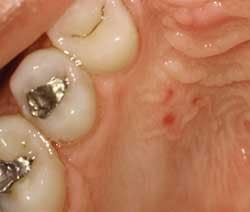

The only findings that you note are three small lesions of varying sizes opposite teeth #4 and #5. The areas are flat, non-ulcerated, red, and circumscribed. (see Figure 1). You show the patient the area in his mouth using a hand mirror and ask him if he has any idea why the lesions might have occurred. The patient responds that he does not know what might have affected these three areas.

You suggest that he may have eaten something such as a hard substance and caused trauma. After thinking for a moment, he tells you that he did eat a lot of chips at a Super Bowl party two days ago. Although he does not report any discomfort, the trauma theory is probably the most logical, educated assumption for these lesions in this case. This is especially true since his health history is negative and the areas of concern are isolated to one area of the mouth.